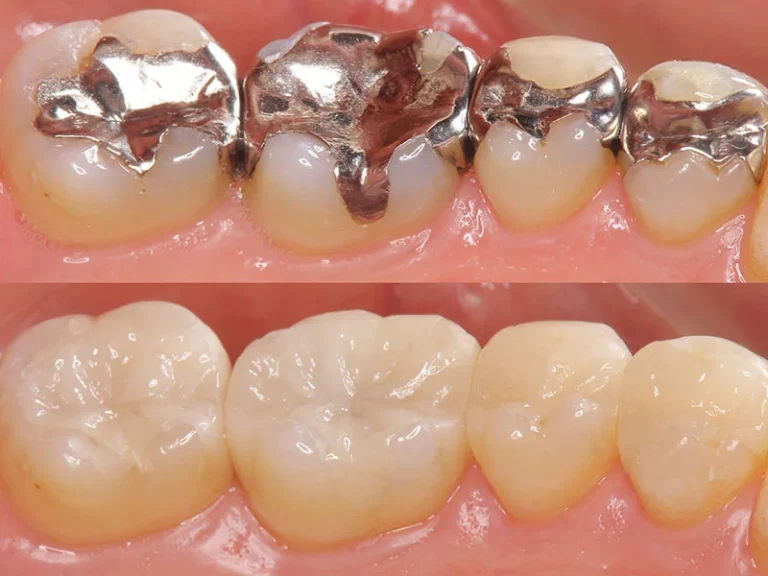

Migliorare l’aspetto del tuo sorriso.

Riparare denti danneggiati o sostituire quelli mancanti.